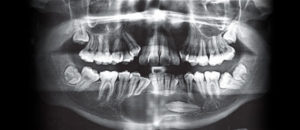

Caso 300 – IDM – HIPERPLASIA DE APÓFISIS CORONOIDES DE LADO DERECHO – IDM

Paciente femenino de 16 años acude al Instituto de Diagnóstico Maxilofacial (sede Miraflores) para evaluación quirúrgica. Radiografia Panorámica A la evaluación de la radiografía panorámica